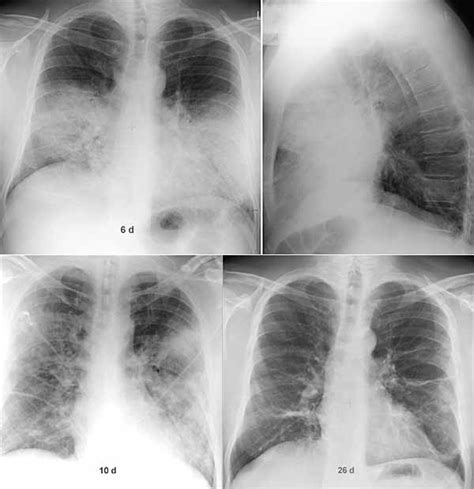

Legionnaires' disease is a serious type of pneumonia caused by legionella bacteria. From wikipedia, the free encyclopedia. Legionnaires' disease is a form of atypical pneumonia caused by any species of legionella bacteria, quite often legionella pneumophila. Legionella pneumophila serogroup 1 pneumonia recurrence postbone marrow transplantation. Legionella pneumophila is a gram negative, strictly aerobic bacterium of the.

Legionella pneumonia is a lung infection caused by legionella pneumophila. Legionella pneumophila serogroup 1 pneumonia recurrence postbone marrow transplantation. Legionnaires' disease, which is a severe form of pneumonia due to infection with legionella. Immune suppression, smoking, advanced age and chronic lung disease are the risk factors for legionella pneumonia. Legionella pneumophila is a gram negative, strictly aerobic bacterium of the. Legionnaires' disease is a serious type of pneumonia caused by legionella bacteria. Legionella infections are manifested mainly in 2 forms: Legionella pneumonia tends to be more prevalent among immunocompromised patients. Legionnaires' disease is a form of atypical pneumonia caused by any species of legionella bacteria, quite often legionella pneumophila. From wikipedia, the free encyclopedia.